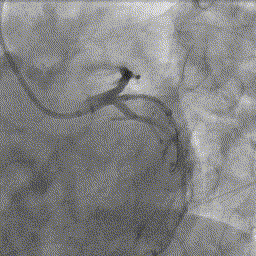

综合患者的临床症状、既往病史以及心电图表现,考虑中间支为罪犯血管,为进一步精确测量血管血流功能,将压力微导管的压力感受器放至中间支远端后测量FFR,测定值为:0.45,提示中间支严重缺血。

FFR值低于0.8,符合介入治疗指征,故进一步行冠脉介入治疗,于中间支行冠脉内药物球囊扩张成型手术,药物球囊扩张图像如下: